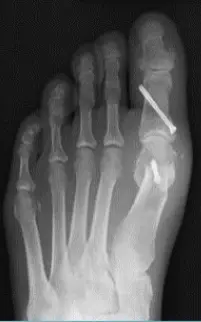

Hallux Valgus

- Definition: lateral deviation of the great toe (hallux) and medial deviation of the first metatarsal

Radiology - Hallux Valgus

- XR views:

- AP standing:

- Lateral deviation of big toe

- Increased varus of 1st MT

- Subluxation of MT-Phal. joint

Treatment - Hallux Valgus

Adult:

- Surgery usually

- Many operations

-

Aim:

- Re-align the 1st metatarsal

- Correct valgus deformity of big toe

- Soft tissue balancing